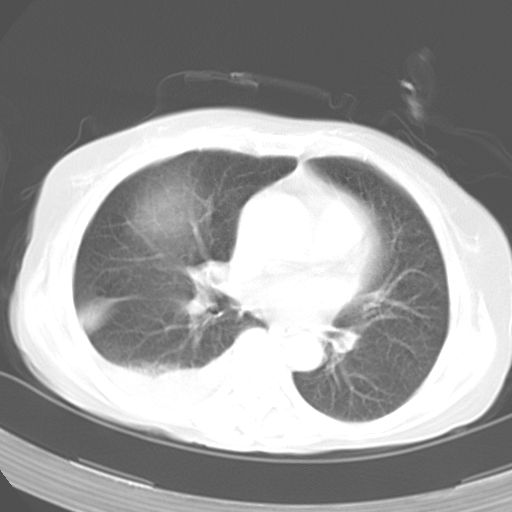

以下是引用dyqct在2006-12-7 21:08:00的发言:[br]考虑:1、肝内外胆管多发性结石伴肝左叶外侧段肝萎缩;[br] 2、右膈下多发脓肿;[br] 3、右侧少量胸腔积液、斜裂积液;[br] 4、左肾囊肿。

以下是引用jiazh在2006-12-7 20:37:00的发言:[br]肝脏周围半狐形低密度影,肝脏表面受压推移,考虑膈下脓肿可能性大;2、右侧胸腔积液

以下是引用拾荒者在2006-12-7 21:44:00的发言:[br]肝内外胆管多发结石,右膈下多发脓肿,右胸膜腔及叶间裂积液,左肾囊肿。[br] [br]